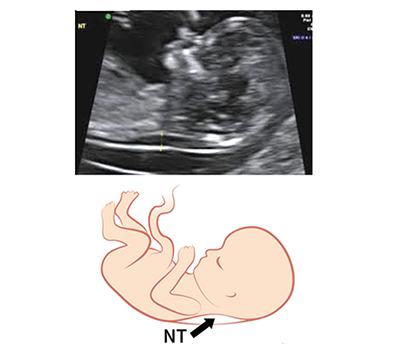

NT(Nuchal Translucency)

NT(エヌ・ティー)とは妊娠初期の超音波検査で胎児の後頚部(うなじの辺り)にみられる浮腫を指します。軽度であれば正常でも認めることはありますが、目立つものはダウン症や13トリソミー、18トリソミーといった染色体異常で多く発生することが知られています。NT測定は特殊な検査ではなく、その異常は一般産科外来で偶然発見されるのですが、正しく評価できる時期は妊娠11週から13週6日までと短く、胎児の向きや位置によって正確に測定できない場合もあります。NTの厚みは35mmが一応の基準値とされています。35mm以下での染色体異常の発生率は0.3%と低いものの、35~44mmでは21%と上昇し、厚みが増えるごとに異常発生率はさらに高くなっていくことが報告されています。大切なことは、NT測定値は染色体異常を疑うひとつの指標に過ぎず、35mm以下であっても異常を伴う場合もあるし、またそれ以上であってもまったく正常であることも多いということです。ですから、たとえNT肥厚だけが単独で認められたとしても、慌てて予断を下すことなく、診断確定のための羊水検査を行うなど慎重を期す必要があります。

イメージ図 NT(Nuchal Translucency)